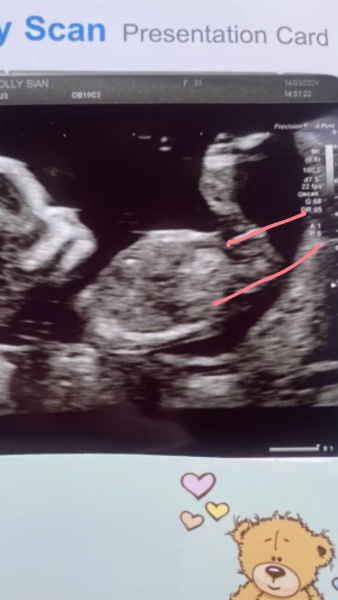

hol92 · 14/03/2024 16:52

Scan all went well feel so much happier and exited 😄 any guessed on girl or boy 🥰

@hol92 i think girl from the nub. I'm no pro though 🤣

What’s the gestation in this photo? Because anything after 12+5, I’m going with girl as the nub is parallel/pointing down 💕

@hol92 According to the theory, boy nubs point upwards/away from the spine from about 12+5 onwards which yours doesn’t.

Don’t swing for me if I’m wrong though 🤣 the nub on my 13 week scan photo is very girly, not a single boy guess, however gender is still unconfirmed meaning I can’t fully back the theory. I already have 2 boys so, we’ll see 😂